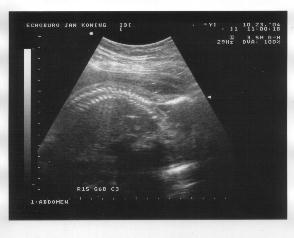

23 oktober 2004

Rechts: Vooraanzicht, gezicht met duidelijk de ogen, neus en mond, en 2 vuistjes